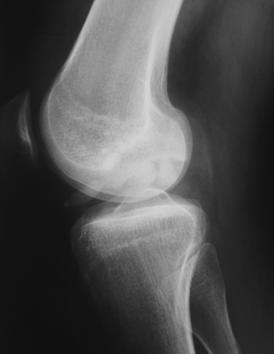

1.2.1. Radiografia standard

Radiografia standard are un rol limitat in evaluarea leziunilor cartilajului articular. Cu toate acestea, radiografia este o examinare de rutina in patologia genunchiului, care poate aduce informatii utile pentru diagnosticarea leziunilor condrale si a patologiei asociate cu acestea.

Radiografiile standard evidentiaza ingustarea spatiului articular, dezaxari, osteofitoza, scleroza subcondrala, chiste subcondrale, deformari ale suprafetelor articulare si ale articulatiei in artroza De asemenea, largirea spatiului articular (cresterea) a fost asociat cu scaderea simptomatologiei artrozice [11].

In osteocondrita disecanta se evidentiaza scleroza subcondrala si fragmentele osteocondrale detasate (fig. 1.3),

Fig. 1.3 Radiografii degenunchi incidente AP si LL - fragmente osteocondrale in osteocondrita disecanta a condilului femural extern, unul dintre ele migrat anterior a determinat blocajul genunchiului |